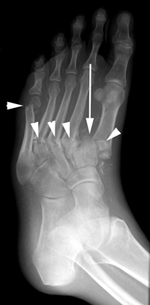

Radiografías. Las radiografías brindan imágenes detalladas de las estructuras densas, como los huesos. En la etapa muy temprana de Charcot, las imágenes proporcionadas por las radiografías pueden ser normales. Sin embargo, en casos más graves, pueden verse fracturas y fragmentos óseos en las radiografías. A medida que avanza la afección, las deformidades pueden volverse más drásticas, lo que puede derivar en luxaciones, destrucción de las articulaciones y formación de tejido óseo.

- Las fracturas inestables y las luxaciones también requieren cirugía para consolidarse.

- Corrección de deformidades en el pie de Charcot. Cuando las fracturas y luxaciones son inestables o los huesos están significativamente desalineados, puede ser necesaria la colocación de placas, tornillos o barras para corregir las deformidades y lograr que los huesos se consoliden en una posición adecuada. Debido a la calidad ósea deficiente, las fracturas que ocurren en los diabéticos suelen ser más complejas. Por lo tanto, las cirugías para corregirlas suelen requerir más implantes (placas y tornillos) que los que serían necesarios en pacientes no diabéticos. Si se realiza cualquiera de estas operaciones, también puede utilizarse un injerto de hueso para ayudar a que los huesos se consoliden.